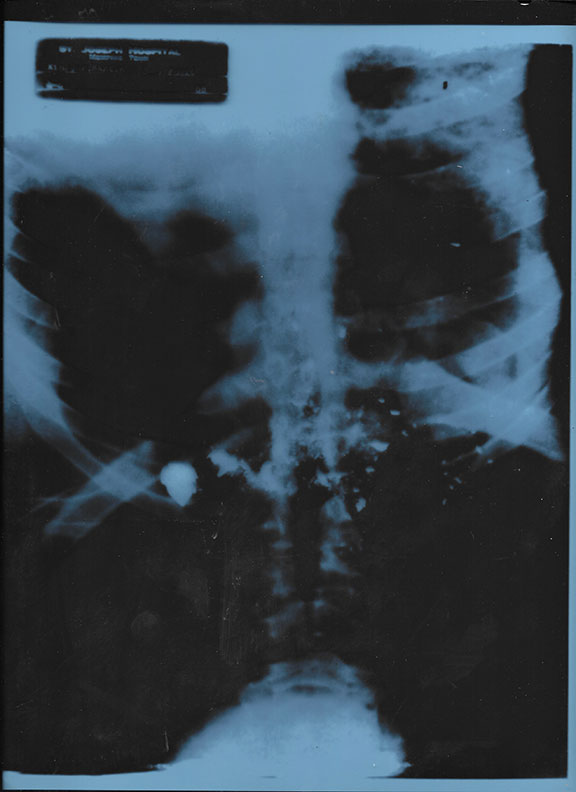

Martin Luther King. Jr. - X-Ray used in Court

KING, JR., Martin Luther (1929-1968). American activist, most visible spokesperson, and leader for the civil rights movement. Assassinated. Man of the year Time Magazine, 1963. Youngest man to receive Nobel Peace Prize, 1964. Original X-Ray, one of several made by St. Joseph’s Hospital, Memphis, Tennessee of the chest of Martin Luther King, Jr. that was used in Court against James Earl Ray. Measures 10”x12” and is in fine condition. This treasure is one of several X-Ray’s that were sold including Julian’s Auction House who got as much as $30,000 each. Still exceptionally scarce and would look magnificent when framed with a photograph and a light over it....................$750.00